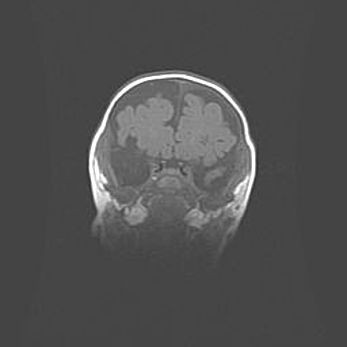

Наружная гидроцефалия с возможной атрофией височных областей.

Возраст: 28 дней

Вес: 3670 г

Пол: мужской

Окружность головы: 38 см

Срок гестации: 40 недель

Гидроцефалия головного мозга у новорожденных – это заболевание, которое характеризуется скоплением избыточного количества спинномозговой жидкости в желудочковой системе головного мозга в результате затруднения её перемещения от места выработки к месту поглощения в кровеносную систему или вследствие нарушения абсорбции. При открытой наружной форме гидроцефалии у новорожденных расширяются и переполняются субарахноидные пространства.

При нормотензивных  формах,  которые,  как  правило,  являются  следствием  перенесенных ишемических  повреждений  паренхимы  мозга,  возможно  сочетание микроцефалии  с нормотензивной гидроцефалией. В основе данных изменений лежит атрофия больших полушарий с преимущественной  локализацией  в  лобно-височных  областях.